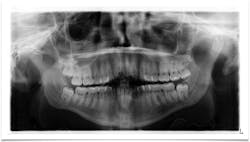

The same patient presents with this chief complaint: “Pain in lower right side of jaw that has progressively been getting worse over the course of the last two to three months; it feels like I have an infection in my wisdom tooth."

A panoramic is taken, and a large radiolucent lesion is noted to extend from the distal of no. 1 to the distal of no. 32. A significant amount of bone destruction in the mandible is observed. Furthermore, a radiolucency is present distal to the crown on no. 17. Clinically, there is inflamed tissue circa on partially erupted no. 32 that extends up to the distal of no. 2. The area is tender to palpation and unremarkable extraorally (figure 2).